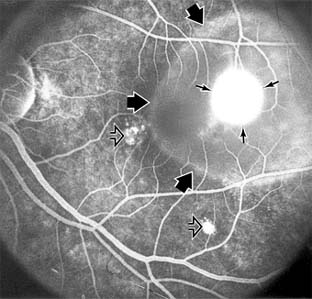

Chapter 10: Retina DISEASES OF THE MACULA AGE-RELATED MACULAR DEGENERATION Age-related macular degeneration is the leading cause of permanent blindness in the elderly. The exact cause is unknown, but the incidence increases with each decade over age 50. Other associations besides age include race (usually Caucasian), sex (slight female predominance), family history, and a history of cigarette smoking. The disease includes a broad spectrum of clinical and pathologic findings that can be classified into two groups: nonexudative ("dry") and exudative ("wet"). Although both types are progressive and usually bilateral, they differ in their manifestations, prognosis, and management. The more severe exudative form accounts for approximately 90% of all cases of legal blindness due to age-related macular degeneration. 1. NONEXUDATIVE MACULAR DEGENERATION Nonexudative age-related macular degeneration is characterized by variable degrees of atrophy and degeneration of the outer retina, retinal pigment epithelium, Bruch's membrane and choriocapillaris. Of the ophthalmoscopically visible changes in the retinal pigment epithelium and Bruch's membrane, drusen are the most typical (Figure 10-1). Drusen are discrete, round, yellow-white deposits of variable size beneath the pigment epithelium and are scattered throughout the macula and posterior pole. With time, they may enlarge, coalesce, calcify, and increase in number. Histopathologically, most drusen consist of focal collections of eosinophilic material lying between the pigment epithelium and Bruch's membrane; they therefore represent focal detachment of the pigment epithelium. In addition to drusen, clumps of pigment irregularly dispersed within depigmented areas of atrophy may progressively appear throughout the macula. The level of associated visual impairment is variable and may be minimal. Fluorescein angiography demonstrates irregular patterns of retinal pigment epithelial hyperplasia and atrophy. Electrophysiologic testing in most patients is normal. There is no generally accepted treatment or means of prevention of this type of macular degeneration. Laser retinal photocoagulation appears to have a beneficial effect on drusen but has not yet been shown to improve visual outcome. Although high plasma levels of antioxidants are associated with a reduced risk of age-related macular degeneration, the use of vitamin supplements does not appear to be preventive. Most patients with macular drusen never experience significant loss of central vision; the atrophic changes may stabilize or progress slowly. However, the exudative stage may develop suddenly at any time, and in addition to regular ophthalmic examinations, patients are given an Amsler grid ( 2. EXUDATIVE MACULAR DEGENERATION Although patients with age-related macular degeneration usually manifest nonexudative changes only, the majority of patients who experience severe vision loss from this disease do so from the development of subretinal neovascularization and related exudative maculopathy. Serous fluid from the underlying choroid can leak through small defects in Bruch's membrane, causing focal detachment of the pigment epithelium. Additional fluid may lead to further separation of the overlying sensory retina, and vision usually decreases if the fovea is involved. Retinal pigment epithelial detachments may spontaneously flatten, with variable visual results, and leave a geographic area of depigmentation at the involved site. Ingrowth of new vessels from the choroid into the subretinal space is the most important change that predisposes patients with drusen to macular detachment and irreversible loss of central vision. These new vessels grow in a flat cartwheel or sea-fan configuration away from their site of entry into the subretinal space. The clinical changes of early subretinal neovascularization are subtle and may be easily overlooked; during this occult stage of new vessel formation, the patient is asymptomatic, and the new vessels may not be apparent either ophthalmoscopically or angiographically. The ophthalmologist must maintain a high index of suspicion that subretinal neovascularization is present whenever a patient with evidence of age-related macular degeneration has sudden or recent central vision loss, including blurred vision, distortion, or a new scotoma. If the fundus examination reveals subretinal blood, exudate, or a grayish-green choroidal lesion in the macula, there is great likelihood that neovascularization is present, and a fluorescein or indocyanine green angiogram should be obtained promptly to determine if a treatable lesion can be identified. Although some subretinal neovascular membranes may spontaneously regress, the natural course of subretinal neovascularization in age-related macular degeneration is toward irreversible loss of central vision over a variable period of time. The sensory retina may be damaged by long-standing edema, detachment, or underlying hemorrhage. Furthermore, a hemorrhagic detachment of the retina may undergo fibrous metaplasia, resulting in an elevated subretinal mass called a disciform scar. This elevated fibrovascular mound of variable size represents the cicatricial end stage of exudative age-related macular degeneration. It is usually centrally located and results in permanent loss of central vision. Treatment In the absence of subretinal neovascularization, no medical or surgical treatment of serous retinal pigment epithelial detachment is of proved benefit. The use of parenteral alpha interferon, for example, has not been effective for this disease. However, if a well-defined extrafoveal ( Krypton laser photocoagulation of juxtafoveal (<200 Following successful photocoagulation of a subretinal neovascular membrane, recurrent neovascularization either contiguous with or remote from the laser scar may occur in one-half of cases by 2 years. Recurrence is often accompanied by severe vision loss, so that careful monitoring with Amsler grids, ophthalmoscopy, and angiography is essential. Low-dose radiotherapy has provided encouraging results in patients with subfoveal neovascularization. Patients with impaired central vision in both eyes may benefit from a variety of low vision aids. CENTRAL SEROUS CHORIORETINOPATHY Central serous chorioretinopathy is characterized by serous detachment of the sensory retina as a consequence of focal leakage of fluid from the choriocapillaris through a defect in the retinal pigment epithelium (Figures 10-2 and 10-3). This disease typically affects young to middle-aged men and may be related to life stress events. Most patients present with the sudden onset of blurred vision, micropsia, metamorphopsia, and central scotoma. Visual acuity is often only moderately decreased and may be improved to near-normal with a small hyperopic correction. The diagnosis is made by slitlamp examination of the fundus; the presence of serous detachment of the sensory retina in the absence of ocular inflammation, subretinal neovascularization, an optic pit, or a choroidal tumor is diagnostic. The retinal pigment epithelial lesion appears as a small, round or oval, yellowish-gray spot that is variable in size and may be difficult to detect without the aid of fluorescein angiography. Fluorescein dye leaking from the choriocapillaris may accumulate below the pigment epithelium or sensory retina, resulting in a variety of patterns including the well-recognized smokestack configuration. Approximately 80% of eyes with central serous chorioretinopathy undergo spontaneous resorption of subretinal fluid and recovery of normal visual acuity within 6 months after the onset of symptoms. Despite normal acuity, however, many patients have a mild permanent visual defect, such as a decrease in color sensitivity, micropsia, or relative scotoma. Twenty to 30 percent of patients will have one or more recurrences of the disease, and complications-including subretinal neovascularization and chronic cystoid macular edema-have been described in patients with frequent and prolonged serous detachments. The cause of central serous chorioretinopathy is unknown; there is no convincing evidence that the disease is either infectious or due to retinal pigment epithelial dystrophy. Argon laser photocoagulation directed to the active leak significantly shortens the duration of the sensory detachment and hastens the recovery of central vision, but there is no evidence that prompt photocoagulation reduces the chance of permanent loss of visual function. Although the complications of retinal laser photocoagulation are few, it is probably not advisable to recommend immediate photocoagulation treatment in all patients with central serous chorioretinopathy. The duration and location of disease, the condition of the fellow eye, and occupational visual requirements are all considerations upon which treatment decisions are based. MACULAR EDEMA Retinal edema involving the macula may be associated with a variety of intraocular inflammatory diseases, retinal vascular diseases, intraocular surgery, inherited or acquired retinal degenerations, medications, macular membranes, or unknown causes. Macular edema may be diffuse, with nonlocalized intraretinal fluid causing thickening of the macula. When edema fluid accumulates in honeycomb-like spaces of the outer plexiform and inner nuclear layers, it is called cystoid macular edema. On fluorescein angiography, fluorescein dye leaks from the perifoveal retinal capillaries and accumulates in a flower-petal pattern about the fovea (Figure 10-4). The most widely recognized association with cystoid macular edema is intraocular surgery. Approximately 50% of eyes undergoing uneventful intracapsular cataract extraction and 20% of eyes undergoing extracapsular cataract extraction develop angiographic cystoid macular edema. Clinically significant edema usually occurs within 4-12 weeks postoperatively, but in some instances its onset may be delayed for months or years. Many patients with cystoid macular edema of less than 6 months' duration have self-limited leakage that will resolve without treatment. Topical or local (or both) anti-inflammatory therapy may be of value in restoring visual acuity in some patients with chronic postoperative macular edema. YAG laser vitreolysis (see Chapter 24) and surgical vitrectomy may be of benefit when the macular edema is associated with vitreous tissue incarcerated in the cataract wound or adherent to anterior segment structures. When an intraocular lens implant is the cause of postoperative macular edema due to its design, positioning, or inadequate fixation, removal of the lens implant can be considered. INFLAMMATORY DISORDERS INVOLVING THE MACULA Presumed Ocular Histoplasmosis Syndrome (Figures 10-5, 10-6 and 10-7) In this disease, serous and hemorrhagic detachments of the macula are associated with multiple peripheral atrophic chorioretinal scars and peripapillary chorioretinal scarring (see Chapter 7). The syndrome usually occurs in healthy patients between the third and sixth decades of life, and the scars are probably caused by an antecedent subclinical systemic infection with Histoplasma capsulatum. The macular detachments are due to subretinal neovascularization, and the visual prognosis depends on the proximity of the neovascular membrane to the center of the fovea. If the membrane extends inside the foveal avascular zone, only 15% of eyes will retain 20/40 vision. A macular scar may change over time, and 10% of patients with normal maculae will develop new atrophic scars in this region. The relative risk of developing macular subretinal neovascularization in the second eye of an affected patient is significant, and these patients should be instructed in the frequent use of the Amsler grid and the importance of prompt examination when changes are detected. Argon laser photocoagulation of a subretinal neovascular membrane outside the foveal avascular zone in symptomatic patients is of value in preventing severe vision loss. The surgical removal of submacular membranes may prove useful in preserving vision. Acute Multifocal Posterior Placoid Pigment Epitheliopathy (AMPPPE) AMPPPE typically affects healthy young patients who develop rapidly progressive bilateral vision loss in association with ophthalmoscopically visible multifocal flat gray-white subretinal lesions involving the pigment epithelium (Figure 10-8). The cause of this disease, which in many instances is associated with evidence of an influenza-like illness, is unknown; the course and nature of the illness suggests the possibility of viral infection. The characteristic feature of the disease is the rapid resolution of the fundus lesions and a delayed return of visual acuity to near-normal levels. Although the prognosis for visual recovery in this acute self-limited disease is good, many patients will identify small residual paracentral scotomas when carefully tested. Extensive pigmentary changes remaining during the late stages of AMPPPE may mimic widespread retinal degeneration; the clinical history and normal electrophysiologic findings aid in this differential diagnosis. Geographic Helicoid Peripapillary Choroidopathy This is a chronic progressive and recurrent multifocal inflammatory disease of the retinal pigment epithelium, choriocapillaris, and choroid. It characteristically involves the juxtapapillary retina and extends radially to involve the macula and peripheral retina. The active stage manifests itself as sharply demarcated gray-yellow lesions with irregular borders that appear to involve the pigment epithelium and choriocapillaris. Vitritis, anterior uveitis, and subretinal neovascularization have been associated with this disorder. Involvement is usually bilateral, and the cause is unknown. The natural history of this indolent inflammatory disease is variable and may correlate with the presence of disease in the fellow eye. Local or systemic corticosteroid treatment may be of benefit when active inflammation is present; laser photocoagulation is administered as indicated for the complication of subretinal neovascularization. Vitiliginous Chorioretinitis (Birdshot Retinochoroidopathy) This is a syndrome characterized by diffuse cream-colored patches at the level of the pigment epithelium and choroid, retinal vasculitis associated with cystoid macular edema, and vitritis. The associations with HLA-A29 and with retinal S-antigen suggest that this disease has a genetic predisposition and that retinal autoimmunity plays a role in its manifestations. In many cases, electroretinography, electro-oculography, and dark adaptation studies are abnormal. The course of the disease is that of exacerbation and remission with variable visual outcomes; visual loss has been attributed to chronic cystoid macular edema, optic atrophy, macular scarring, or subretinal neovascularization. Corticosteroid therapy has not proved effective against this disease. Acute Macular Neuroretinopathy Acute macular neuroretinopathy is characterized by the acute onset of paracentral scotomas and mild visual acuity loss accompanied by wedge-shaped parafoveal retinal lesions in the deep sensory retina of one or both eyes. The macular lesions are subtle, reddish-brown, and best seen with a red-free light. The patients are usually young adults with a history of acute viral illness. While the retinal lesions may fade, the scotomas tend to persist and remain symptomatic. Multiple Evanescent White Dot Syndrome This is an acute and self-limited unilateral disease that affects mainly young women and is characterized clinically by multiple white dots at the level of the pigment epithelium, vitreal cells, and transient electroretinographic abnormalities. The cause is unknown. There is no evidence of associated systemic disease. The retinal lesions gradually regress in a matter of weeks, leaving only minor retinal pigment epithelial defects. ANGIOID STREAKS Angioid streaks appear as irregular, jagged tapering lines that radiate from the peripapillary retina into the macula and peripheral fundus (Figure 10-9). The streaks represent linear crack-like dehiscences in Bruch's membrane. The lesions are rarely noted in children and probably develop in the second or third decade of life. Early in the disease the streaks are sharply outlined and red-orange or brown. Subsequent fibrovascular tissue growth may partially or totally obscure the streak margins. Nearly 50% of patients with angioid streaks have an associated systemic disease. Pseudoxanthoma elasticum, Paget's disease of bone, Ehlers-Danlos syndrome, and several hemoglobinopathies and hemolytic disorders have been associated with this retinal disease, but the most common association is with age-related degeneration of Bruch's membrane. Patients with angioid streaks should be warned of the potential risk of choroidal rupture from even relatively mild eye trauma. Older patients with the disease are at risk of developing serous and hemorrhagic detachments of the retina as a consequence of subretinal neovascularization. Laser treatment may be used to photocoagulate extrafoveal neovascular membranes; however, other neovascular membranes are likely to occur. Prophylactic treatment of angioid streaks before subretinal neovascularization develops is not recommended. MYOPIC MACULAR DEGENERATION Pathologic myopia is one of the leading causes of blindness in the United States and is characterized by progressive elongation of the eye with subsequent thinning and atrophy of the choroid and pigment epithelium in the macula. Peripapillary chorioretinal atrophy and linear breaks in Bruch's membrane ("lacquer cracks") are characteristic findings on ophthalmoscopy (Figure 10-10). The degenerative changes of the macular pigment epithelium resemble those found in the older patient with age-related macular degeneration. A characteristic lesion of this disease is a raised, circular, pigmented macular lesion called a Fuchs spot. Most patients are in the fifth decade when the degenerative macular changes cause a slowly progressive loss of vision; rapid loss of visual acuity is usually caused by serous and hemorrhagic macular degeneration overlying a subretinal neovascular membrane. Fluorescein angiography in patients with pathologic myopia may show delayed filling of choroidal and retinal blood vessels. Angiography is helpful in identifying and locating the site of subretinal neovascularization in patients who develop serous or hemorrhagic detachments of the macula. Because of the frequent close proximity of the subretinal neovascular membrane to the foveola in these patients, laser photocoagulation may not be possible. As subretinal neovascular membranes tend to remain small and because photocoagulation-associated chorioretinal atrophy tends to progress in patients with pathologic myopia, retinal laser treatment is not as beneficial as in other diseases associated with macular subretinal neovascularization. The chorioretinal changes of pathologic myopia predispose the retina to breaks and thus to retinal detachment. Peripheral retinal findings may include paving stone degeneration, pigmentary degeneration, and lattice degeneration. Retinal breaks usually occur in areas involved with chorioretinal lesions, but they also arise in areas of apparently normal retina. Some of these breaks, particularly those of the "horseshoe" and round retinal tear type, will progress to rhegmatogenous retinal detachment. MACULAR HOLE A macular hole is a partial or full-thickness absence of the sensory retina in the macula. This disorder occurs most often in elderly women and is associated with elevated plasma fibrinogen levels. The typical finding on biomicroscopy of the symptomatic eye is a full-thickness, round or oval, sharply defined hole measuring one-third disk diameter in the center of the macula, which may be surrounded by a ring detachment of the sensory retina (Figure 10-11). With a full-thickness macular hole, visual acuity is impaired and metamorphopsia, as well as a central scotoma, are present on the Amsler grid. An operculum of retinal tissue may overlie the macular hole. Tangential traction from epiretinal vitreous cortex plays an important role in the pathogenesis of macular hole. Early stages of macular hole formation, such as a deep foveal yellow spot or ring, may be reversible as the posterior vitreous cortex spontaneously separates from the retina. Therapy for macular hole disease involves reattaching and potentially restoring function to the retina overlying the cuff of subretinal fluid surrounding the hole. While the anatomic results of vitrectomy surgery to close macular holes are encouraging, the clinical benefits are still under study. EPIRETINAL MACULAR MEMBRANES Fibrocellular membranes may proliferate on the surface of the retina, either in the macula or peripheral retina. Contraction or shrinkage of these epiretinal membranes may cause varying degrees of visual distortion, intraretinal edema, and degeneration of the underlying retina. Biomicroscopy usually shows retinal wrinkles and vessel tortuosity and may rarely also show retinal hemorrhages, cotton-wool spots, serous retinal detachment, and macular hole; a posterior vitreous detachment is nearly always present (Figure 10-12). Disorders associated with epiretinal membranes include retinal tears with or without rhegmatogenous retinal detachment, vitreous inflammatory diseases, trauma, and a variety of retinal vascular diseases. Patients with macular distortion and vision loss caused by epiretinal membrane contraction are usually left with stable visual acuity, suggesting that membrane contraction is a short-lived and self-limited process. Surgical peeling of severe epiretinal membranes can be performed successfully, but regrowth of epiretinal tissues occurs in some cases. There is no role for photocoagulation in the treatment of epiretinal macular membrane disease. TRAUMATIC MACULOPATHY Blunt trauma to the anterior segment of the eye may cause a contrecoup injury to the retina called commotio retinae. The retina develops a gray-white color that affects primarily the outer retina and may be confined to the macular area (Berlin's edema) or may involve extensive areas of the peripheral retina. The retinal whitening in the macular area may clear completely, or impairment of central vision may be permanent and associated with a pigmented retinal scar (Figure 10-13) or a macular hole. Trauma similar to that which causes Berlin's edema may also cause choroidal rupture with subretinal hemorrhage and permanent central vision loss. In addition to blunt trauma, several other traumatic injuries involving the macula are of importance. Purtscher's retinopathy is characterized by multiple patches of superficial retinal whitening and retinal hemorrhages in each eye of a patient after severe compression injury to the head or trunk. Terson's syndrome is seen in approximately 20% of patients after traumatic (or spontaneous) subarachnoid or subdural hemorrhage and is characterized by vitreous and superficial macular hemorrhage. Solar retinopathy refers to a specific foveolar lesion that occurs after sun-gazing and is best described as a usually bilateral sharply circumscribed and often irregularly shaped partial-thickness hole or depression in the center of the fovea. MACULAR DYSTROPHIES Macular dystrophies differ from degenerations in that the former are inherited, though not necessarily evident at birth, and are not associated with systemic diseases. Most often the disorder is restricted to the macula; it may be symmetric or asymmetric, but eventually both eyes are affected. In the early stages of some of these disorders the visual acuity may be reduced while the macular changes are subtle or absent on ophthalmoscopy, and the patient's complaint may be dismissed as spurious. Conversely, in other macular dystrophies, the ophthalmoscopic changes may be very striking at a time when the patient is free of visual symptoms. One method of classifying the more common macular dystrophies is to consider the presumptive anatomic layer or layers of the retina involved (Table 10-1). X-Linked Juvenile Retinoschisis This is a congenital disease of males characterized by a macular lesion called "foveal schisis." On slitlamp examination, foveal schisis appears as small superficial retinal cysts arranged in a stellate pattern accompanied by radial striae centered in the foveal area (Figure 10-14). Visual acuity is usually between 20/40 and 20/200; peripheral visual field abnormalities are present in the 50% of patients with associated peripheral retinoschisis. The posterior pole appears normal on fluorescein angiography, and this may be helpful in the clinical differentiation from cystoid macular edema. B wave abnormalities on the electroretinogram are consistent with the histopathologic finding of intraretinal splitting in the nerve fiber layer. Cone-Rod Dystrophies The cone-rod dystrophies constitute a relatively rare group of disorders that may be regarded as a single entity showing variable expressivity. Most cases are sporadic, but familial cases are usually transmitted by an autosomal dominant inheritance pattern. Cone-rod dystrophy is characterized by predominant involvement of the cone photoreceptors with progressive color vision defects and associated loss of visual acuity. A bilateral and symmetric bulls-eye pattern of depigmentation and a corresponding zone of hyperfluorescence surrounding a central nonfluorescent spot (similar to that seen in chloroquine retinopathy) are the most commonly described biomicroscopic and angiographic changes in these patients (Figure 10-15). As the disease progresses, the electroretinogram shows marked loss of cone function associated with a slight to moderate loss of rod function. Histopathologic study shows absence of macular and paramacular photoreceptors, and there is associated pigment epithelium degeneration. Fundus Albipunctatus Fundus albipunctatus is an autosomal recessive nonprogressive dystrophy characterized by a myriad of discrete small white dots at the level of the pigment epithelium sprinkled about the posterior pole and midperiphery of the retina. Patients are night-blind with normal visual acuity, normal visual fields, and normal color vision. While the electroretinogram and electro-oculogram are usually normal, dark adaptation thresholds are markedly elevated. Retinitis punctata albescens is the less common progressive variant of this dystrophy. Fundus Flavimaculatus (Stargardt's Disease) This is a bilateral and symmetric autosomal recessive disorder characterized by multiple yellow-white fleck lesions of variable size and shape confined to the retinal pigment epithelium (Figure 10-16). Many patients suffer central visual loss in childhood; however, macular involvement and the ultimate visual outcome are variable. Fluorescein angiography is important in differentiating flecks from drusen; the former are usually hypofluorescent. The electroretinogram and electro-oculogram are usually normal. Histopathologic abnormalities are confined to the pigment epithelium; the yellow flecks seen clinically are dense accumulations of lipofuscin within engorged pigment epithelial cells. Vitelliform Dystrophy (Best's Disease) Vitelliform dystrophy is an autosomal dominant disorder with variable penetrance and expressivity with onset usually in childhood. The ophthalmoscopic appearance is variable and ranges from a mild pigmentary disturbance within the fovea to the typical vitelliform or "egg yoke" lesion located within the central macula (Figure 10-17). This characteristic cyst-like lesion is generally quite round and well demarcated and contains homogeneous opaque yellow material lying at the apparent level of the retinal pigment epithelium. The "egg yoke" may degenerate and be associated with subretinal neovascularization, subretinal hemorrhage, and extensive macular scarring. Visual acuity often remains good, and the electroretinogram is normal; the distinctly abnormal electro-oculogram is the hallmark of this disease. PREVIOUS | NEXT Page: 1 | 2 | 3 | 4 | 5 | 6 | 7 | 8 | 9 10.1036/1535-8860.ch10 |